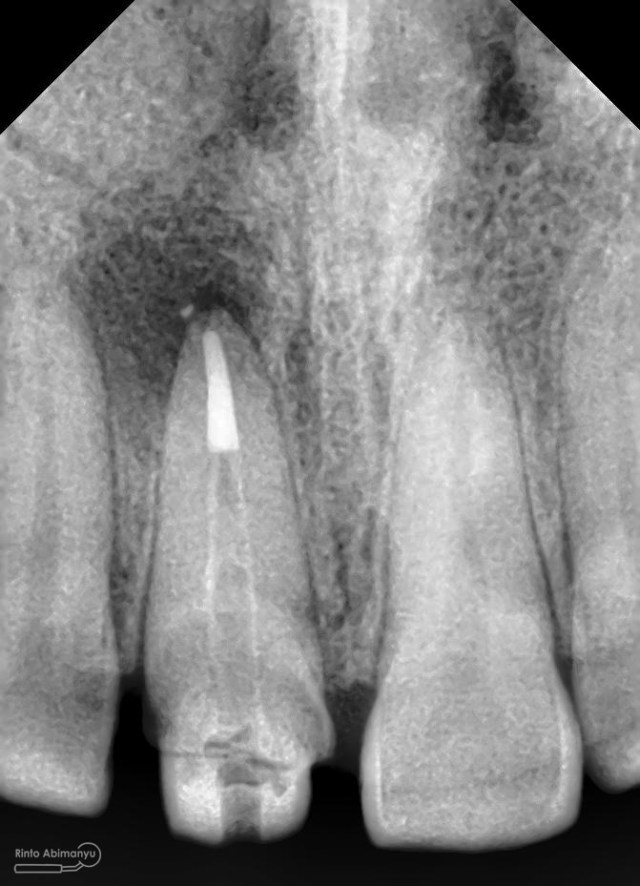

Prosedur sama seperti kemarin memasangkan rubber dam dahulu untuk isolasi daerah kerja, kemudian melakukan akses ke kamar pulpa… Penjajakan awal saluran akar menggunakan K-file nomer 10, dan panjang kerja diukur menggunakan apex locator… Irigasi dan aktivasi masih menggunakan metode yang sama juga… Setelah prosedur cleaning and shaping selesai dilakukan pengepasan guttap dan difoto ronsen…

Foto radiografis trial guttap gigi 22

Nah dari foto ronsen ini juga saya melakukan evaluasi hasil pengisian pada gigi 11 21 nya… alhamdulillah pengisian yang kemarin terlihat sepanjang kerja dan padat serta rapat… Pada gigi 22 nya pun pengepasan guttap terlihat sudah sepanjang kerja…